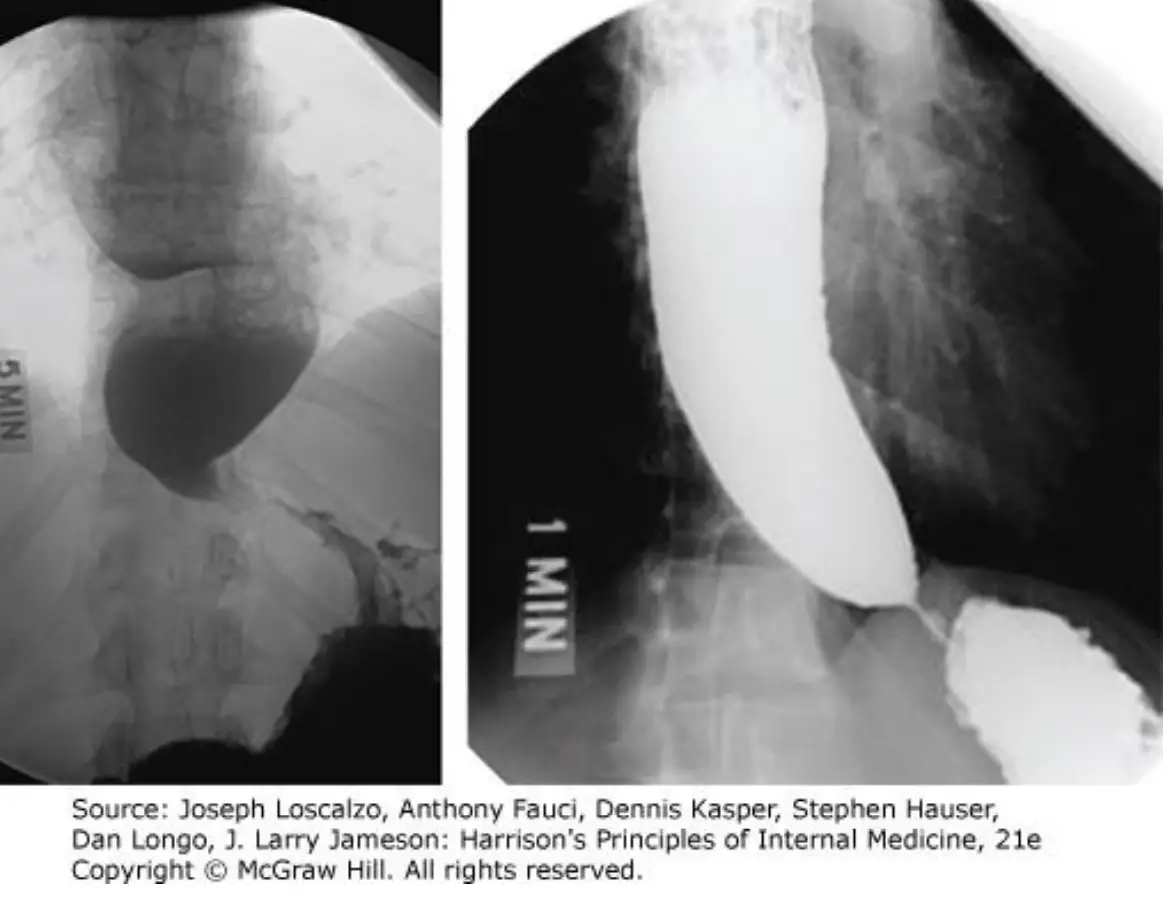

從雙時相(1分鐘與5分鐘)barium swallow可見:

• 食道顯著擴張,集積大量未通過的造影劑,且食道壁平滑無不規則內凹或瘤樣突起。

• 下段食道(LES)出現細長、對稱的「bird’s beak」錐形狹窄,造影劑通過狹窄區後才能進入胃內。

• 停留5分鐘後仍有大量造影劑殘留於食道,代表食道排空功能嚴重障礙。

這些特徵與primary achalasia高度吻合,對於pseudoachalasia(由腫瘤等機械性阻塞引起的類似表現)仍需進一步內視鏡鑑別。